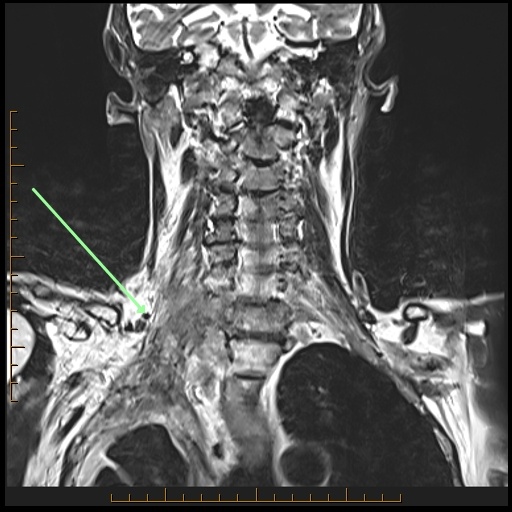

The arrows point to what primary tumor in this 77-year-old male with lung cancer? What’s invaded? Is it cleanly resectable? Come up with your own answers, then check below the images to see my findings.

A Pancoast tumor (arrow) which crosses the cupola (fat pad at lung apex) of the lung, invades the brachial plexus and the vertebra. It is NOT resectable.

ProScan Pearl: Check the lung apex on every cervical spine MRI.